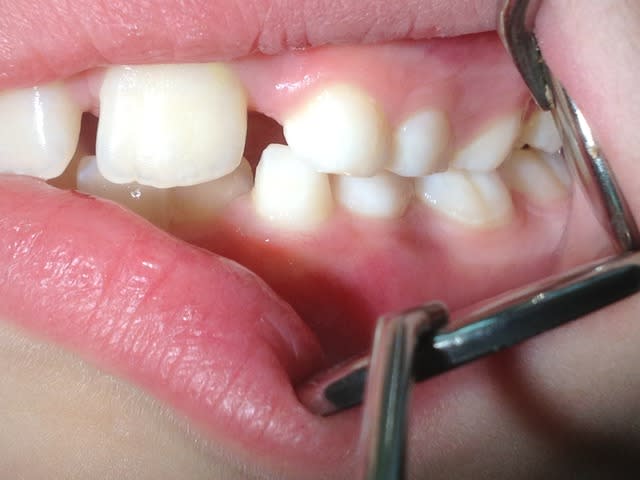

Bonjour! Enfant de pas encore 7ans présentant une DDM.L'ortho me demande d'extraire 53,63,73,83 (c'est la mode dans mon coin!)car manque de place pour la venue de la 12 et 22.Je trouve cela particulièrement traumatisant pour une petite fille de cette age.Ne peut-on pas selon vous passer par d'autres solutions en commençant par exemple à reserrer 11 et 21.

Ci joint la pano et merci pour vos réponses

Re!! voila quelques photos,et que pensez vous de l'ortho qui pense que l'expansion n'est pas possible car il ne s'agit pas d'une endoalveolie??Merci

On ne peut pas dire grand chose avec ces photos, tu nous donnes des photos et des radios du secteur antérieur pour qu'on te donne un avis sur ce qui se passe en postérieur... Ce qui aurait été intéressant ça aurait été de voir la forme du palais par exemple ou au moins l'occlusion sur les secteurs latéraux.

Bref, pour faire simple, là on voit pas grand chose, mais j'ai l'impression sur ta 4eme photo que l'occlusion est inversée à droite... 85 semble plus vestibulaire que son antagoniste, non ? Et du peu qu'on en voit en secteur gauche ça semble être du même genre non ? Regarde la forme du palais : s'il te semble creusé et étroit, ça doit te mettre la puce à l'oreille.

Re!!! Voilà de nouvelles photos, donc pour résumer ,enfant de 7ans auquel l'ortho me demande d'extraire les 4 canines de lait pour laisser la place aux latérales.Probléme ;est ce que l'expansion est possible:Merci de toutes vos réponses